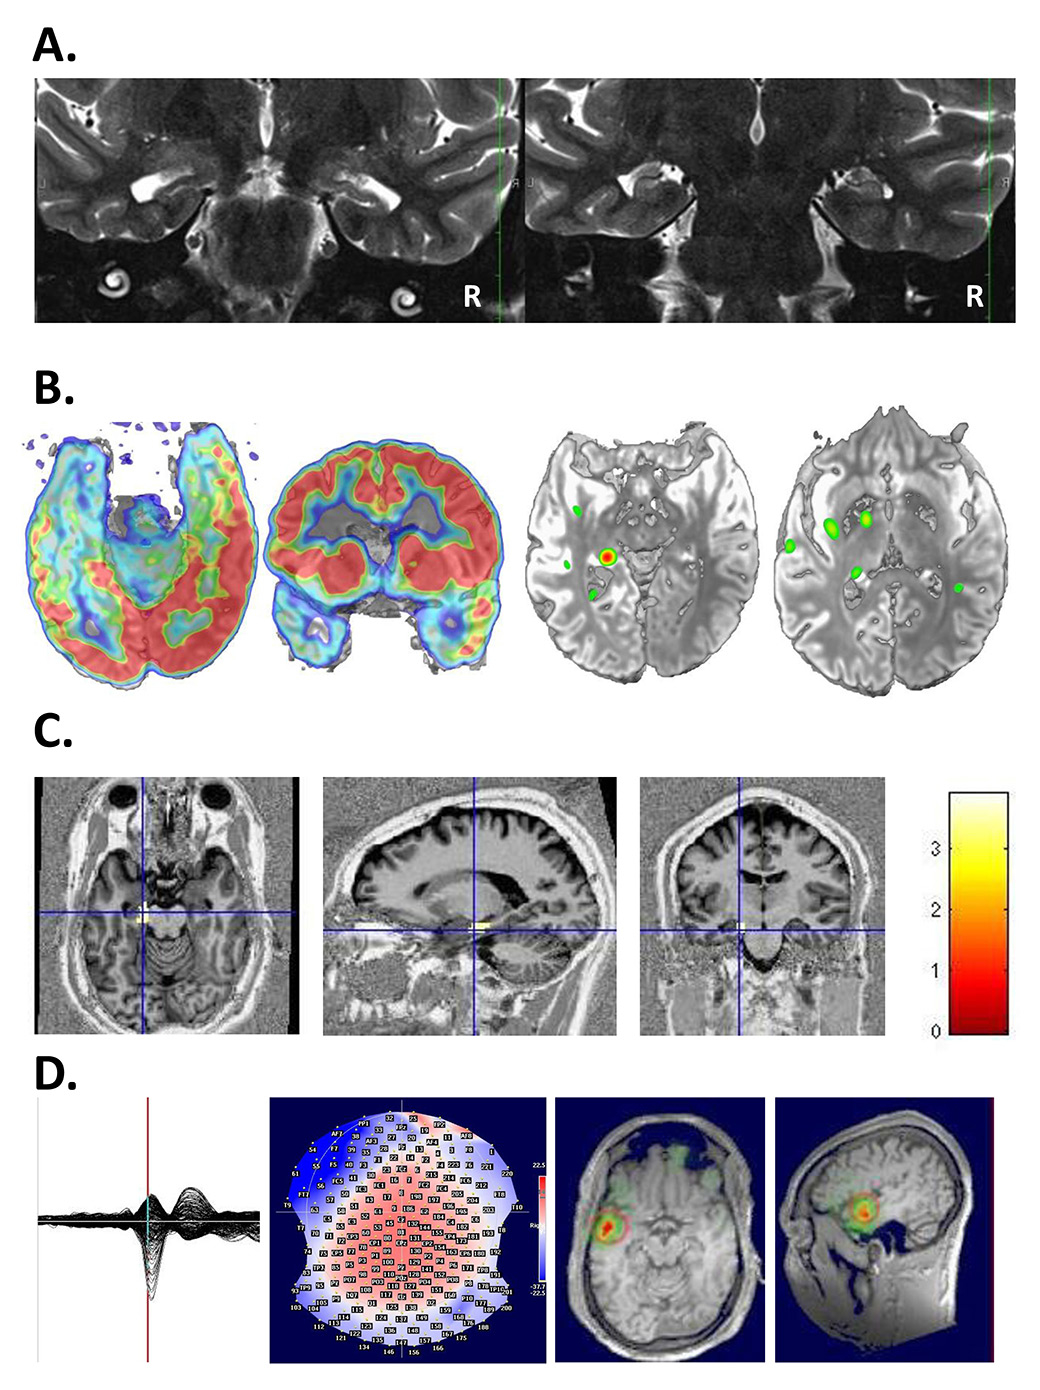

During the evaluation, two basic questions have to be answered: the location of the epileptic focus and identity of possibly adjacent vital cortex. The goal of epilepsy surgery is safe removal of the epileptogenic tissue without inflicting a (new) neurological deficit. Neurological, neuropsychological and psychiatric evaluations are basic elements of the preoperative work-up. The evaluation procedure includes the recording of several habitual seizures with long-term video-EEG monitoring in a specialised centre, with 24-h surveillance by specialised personnel, rapid access to intensive care and emergency CT. A high resolution MRI scan and, if possible, examination with other imaging tools (e.g. position-emission tomography [PET], single photon-emission-computer-tomography [SPECT], high-density EEG / electric source imaging [ESI]) are crucial in the identification of the seizure onset zone [96]. The more imaging examinations are concordant, the more likely there will be postoperative seizure freedom [97]. Figure 2 provides an example of multimodal imaging in a patient with bitemporal discharges.

Surgical results depend critically on the definition of the ictal and interictal EEG onset zone as well as on the presence of a lesion in 1.5-Tesla or, better, 3-Tesla high-resolution MRI, obtained with an epilepsy protocol, i.e. 1 mm slices for most sequences, as detailed elsewhere [98]. If the lesion is highly suspected or functionally localised with PET, SPECT or ESI, but not visualised in the high-resolution MRI, additional statistical analysis of the MRI may be useful and unravel the underlying epileptogenic lesion [99, 100] (fig. 3).

Figure 2

A 26-year-old patient undergoing multimodal imaging after a recording of bitemporal discharges with left predominance. A. MRI showed bilateral hippocampal atrophy with left predominance. B. left: PET showed a hypometabolism at the left mesioteporal lobe, right: Ictal-interictal substraction SPECT (SISCOM) showed an ictal hypermetabolism at the left mesiotemporal lobe. C: Combined EEG-fMRI showed a left hippocampal localization of spike-related BOLD changes. D. Electric source imaging (ESI) also showed a left localisation of spikes. With multimodal work-up left antero-mesial epilepsy was diagnosed.

EEG = electroencephalogram; fMRI = functional MRI; MRI = magnetic resonance imaging; PET = positron emission tomography; SPECT = single photon emission computed tomography. (The left side of the image is left.)